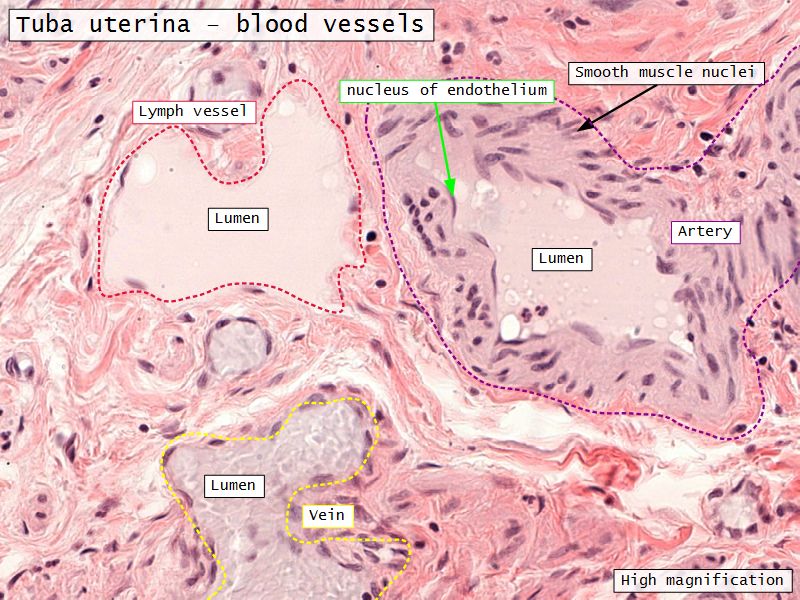

Tuba uterina

Tuba uterina

- Muscular tube

- Most frequent site of fertilization

- Conveys zygote to uterus

- Four regions

- Three layers

Three layers

- Mucosa

- Muscular layer

- Serosa

Muscular layer

Serosa

- Simple squamous epithelium

- Contains

- Blood vessels

- Lymphatics

- Nerves